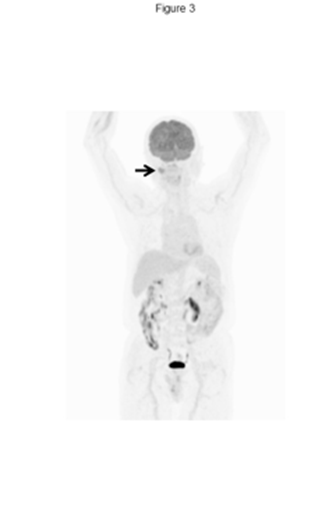

Magnetic resonance imaging (MRI) demonstrated a strongly enhancing, well defined, lobulated T2-hyperintense lesion with an internal reticular pattern (Figure. 2B). 18FDG-PET /CT showed focal uptake in the buccal lesion only (Figure. 3).

Figure 3: FDG-PET/CT images.

18FDG-PET/CT at the initial visit to our department in 2019 demonstrated abnormal 18FDG uptake in the right buccal region (SUVmax 6.53), with no abnormal uptake elsewhere.